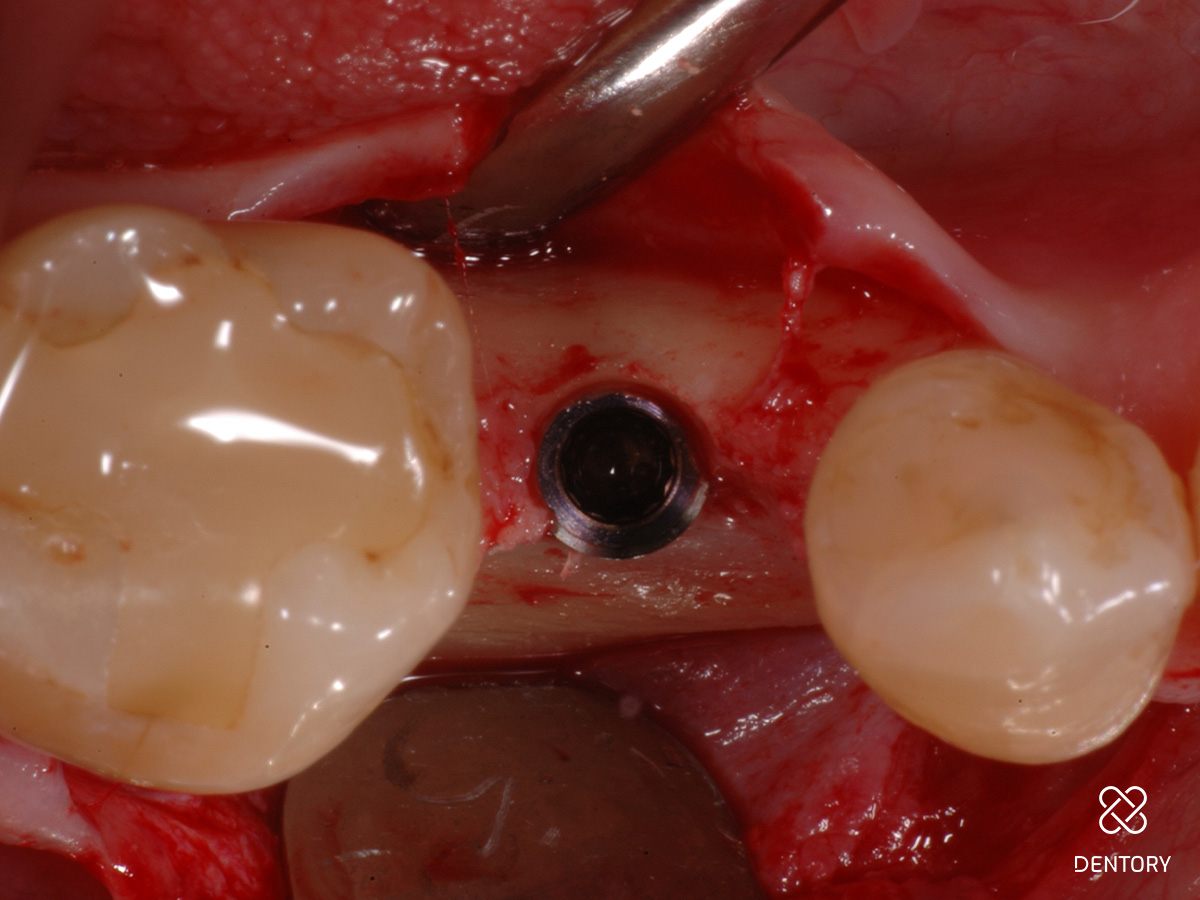

Abbildung 3

Okklusale Ansicht nach Insertion eines 4 mm-Implantats mit Plattform-Switching. Eine simultane Defektrekonstruktion erscheint möglich.